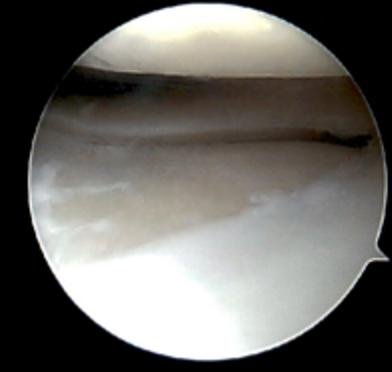

During the procedure, Dr Awwad makes a few small incisions around the knee and inserts a tiny camera (arthroscope) to view the inside of the joint on a monitor. Specialised surgical instruments are then used to repair or remove damaged tissue as needed.

Knee arthroscopy can be used to treat a wide range of knee conditions, such as torn cartilage (meniscus), damaged ligaments, loose bone or cartilage fragments, inflamed joint linings, and patella (kneecap) tracking problems. Because the procedure is performed through small incisions, it generally involves less pain and a quicker recovery than traditional open surgery.

4. Joint inspection and diagnosis